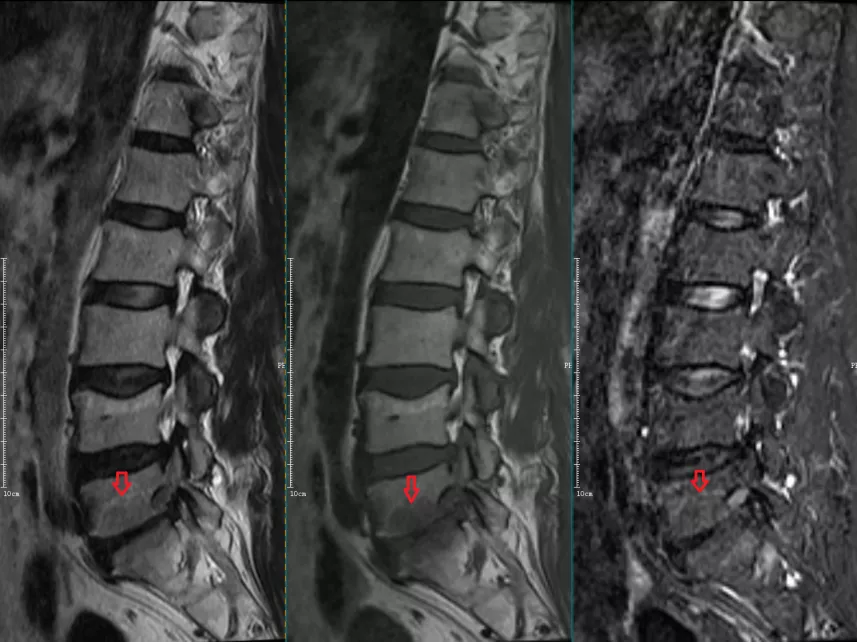

椎体终板炎的mri表现